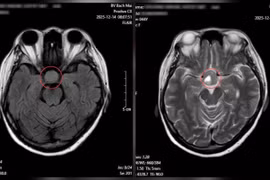

Bất thường ở mắt không ngờ u não khổng lồ

Khuyết thị trường thường tiến triển âm thầm, người bệnh rất khó tự nhận ra, chỉ phát hiện khi tình trạng đã nặng.